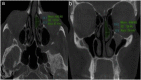

Objectives: The purpose of this study is to describe and assess the short- and long-term efficacy of a modified crushing technique for concha bullosa management.

Methods: Patients who met inclusion criteria underwent a detailed nasal examination and cone beam computed tomography imaging prior to and after septoplasty with crushing surgery for obstructive concha bullosa. Patients were divided into short- and long-term groups based on their followup period such that the short-term group had a mean followup of 15.14 months (range 6-22 months) and the long-term group had a mean followup of 56.66 (range 29-80) months.

Results: Twenty-four cases of obstructive concha bullosa were included in this study with 13 short-term and 11 long-term follow-ups. All patients showed a significantly decreased postoperative CB size (p < 0.001). There was no correlation between age and postoperative CB change in area (p = 0.39) and no significant difference in the amount of postoperative CB area reduction between the short-term and long-term groups (p = 0.35). No patients experienced bleeding, synechia, conchal destruction, or olfactory dysfunction on followup evaluations.

Conclusions: Our modified crushing technique is a simple, effective, and lasting treatment option for concha bullosa. From our experience, there have been no complications and no instances of concha bullosa reformation during the follow-up period.